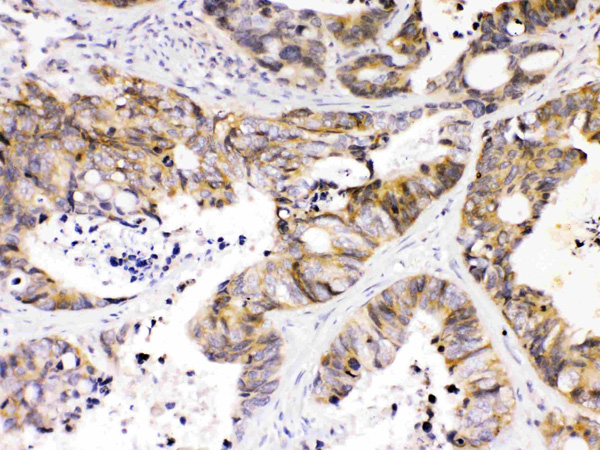

IHC (Immunohistochemistry)

(Figure 4. IHC analysis of NDRG3 using anti- NDRG3 antibody (AAA124744).NDRG3 was detected in paraffin-embedded section of human intestinal cancer tissues. Heat mediated antigen retrieval was performed in citrate buffer (pH6, epitope retrieval solution) for 20 mins. The tissue section was blocked with 10% goat serum. The tissue section was then incubated with 1ug/ml rabbit anti- NDRG3 Antibody (AAA124744) overnight at 4 degree C. Biotinylated goat anti-rabbit IgG was used as secondary antibody and incubated for 30 minutes at 37 degree C. The tissue section was developed using Strepavidin-Biotin-Complex (SABC) with DAB as the chromogen.)